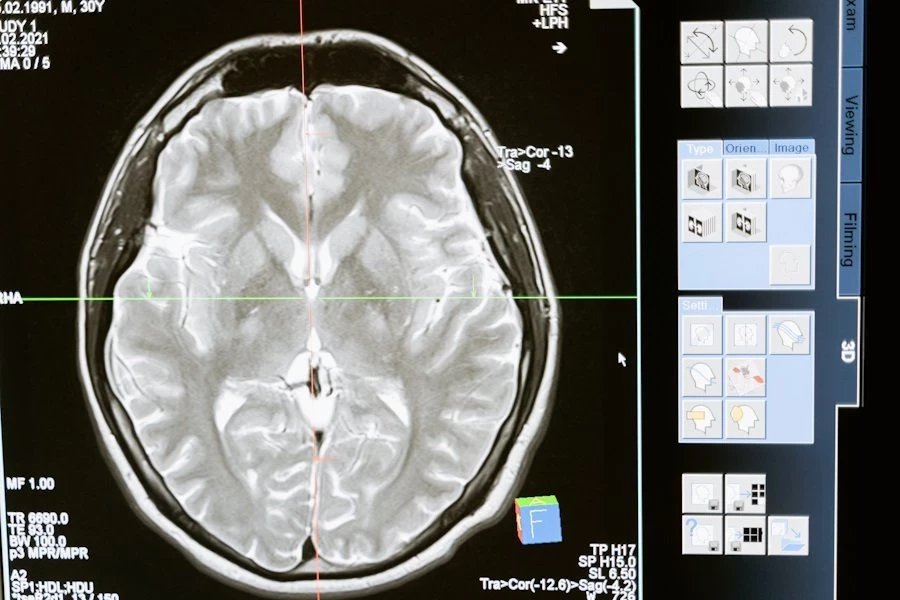

Глиобластома является наиболее распространенной злокачественной первичной опухолью головного мозга. Она чаще всего поражает лобные, височные, теменные и затылочные доли мозга и встречается преимущественно у людей старше 64 лет, причем мужчины страдают от этого заболевания чаще, чем женщины, отмечают ученые УрФУ.